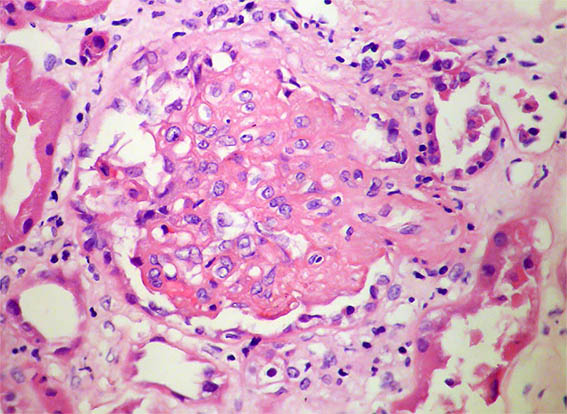

Figura 3.

H&E, X400. Lesión esclerosante segmentaria.